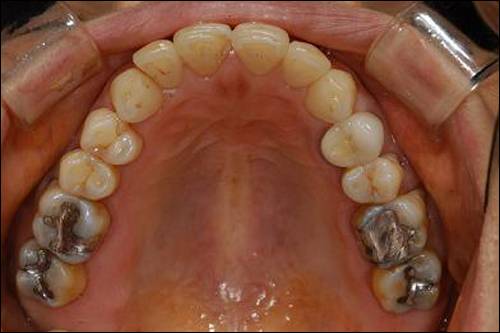

앞니가 아닌 어금니(대구치, 소구치)의 충치를 제거하고 수복하는 재료는 일반적으로 '아말감', '레진', '골드 인레이', '심미(레진, 세라믹 등) 인레이' 이렇게 4가지인데 이 중 유일하게 건강보험의 적용을 받는 재료가 아말감이다.

이런 환자들을 위해 우선 아말감이란 재료에 대해 알아보도록 하자. 아말감은 치과 재료 중 가장 오랫동안 쓰인 것으로 은, 주석, 동을 주성분으로 하는 아말감 합금을 강한 힘으로 분쇄시키면서 수은과 혼합시킨 것을 의미한다. 처음 눈뭉치와 같은 느낌의 아말감을 충치를 제거한 자리에 강한 힘으로 다져 넣는데, 일정 시간이 지나면 이 아말감은 딱딱하게 굳어진다.

결론은 수복재로써 아말감은 안전하다는 이야기다. 더욱이 시술한 지 일정 기간이 지나 있고 현재 별 증상이나 2차 우식의 징후가 없는 아말감을 '수은'을 이유로 다른 재료로 대체하는 것은 경제적으로도 의학적으로도 불합리한 결정이다.

다음으로 하고 싶은 이야기는 재료로써 아말감의 우수함이다. 컴퓨터로 검색해 본 인터넷의 정보에는 실패한 아말감 케이스들이 나와있었다. 그 사진들만 보고 있으면 '아말감은 정말 가난한 사람들이 어쩔 수 없이 선택하는 도저히 못쓸 싸구려 재료'라는 느낌이 들었다.

아말감의 대체재로 사용하는 복합 레진은 중합 수축이라는 단점이 있다. 적은 양이지만 재료의 끝 부분이 줄어든다는 것은 틈이 생긴다는 의미이고 이것은 2차 우식의 가능성을 높인다. 아말감은 반대로 경화 팽창의 과정을 가진다. 이 점만을 가지고 아말감이 레진보다 좋은 재료라고 말하기는 어렵지만 적어도 나름의 장단점을 가진 재료인 것만큼은 확실하다. 10년 이상의 장기 사용을 하고도 2차 우식이 생기지 않은 케이스가 적지 않음을 생각하면 아말감 역시 정확하게만 시술하면 얼마든지 수복재로써의 기능을 다할 수 있는 재료인 것이다.